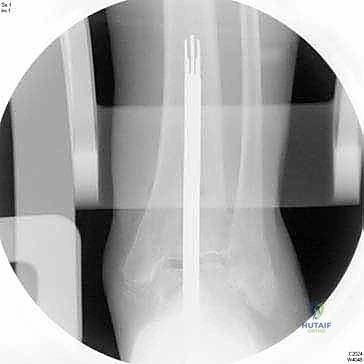

1. التثبيت داخل النقي (Intramedullary Fixation): على عكس المفاصل القديمة التي كانت تعتمد على التثبيت السطحي، يحتوي نظام INBONE على ساق معدنية (Stem) يتم إدخالها داخل القناة النخاعية لعظمة الساق (الظنبوب). هذا يوفر ثباتاً ميكانيكياً استثنائياً ويمنع ارتخاء المفصل بمرور الوقت.

4. إعداد القناة النخاعية وتركيب الساق (Stem)

يتم عمل ثقب دقيق في القناة النخاعية لعظمة الساق. يتم إدخال القطع المعيارية (Modular Stem Pieces) واحدة تلو الأخرى حتى يتم تحقيق التثبيت العميق والمستقر داخل العظم. هذا هو سر قوة نظام INBONE.